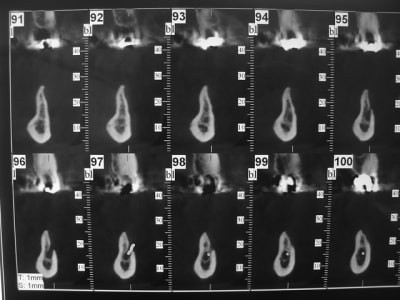

DSC05918_mvy6lu.jpg